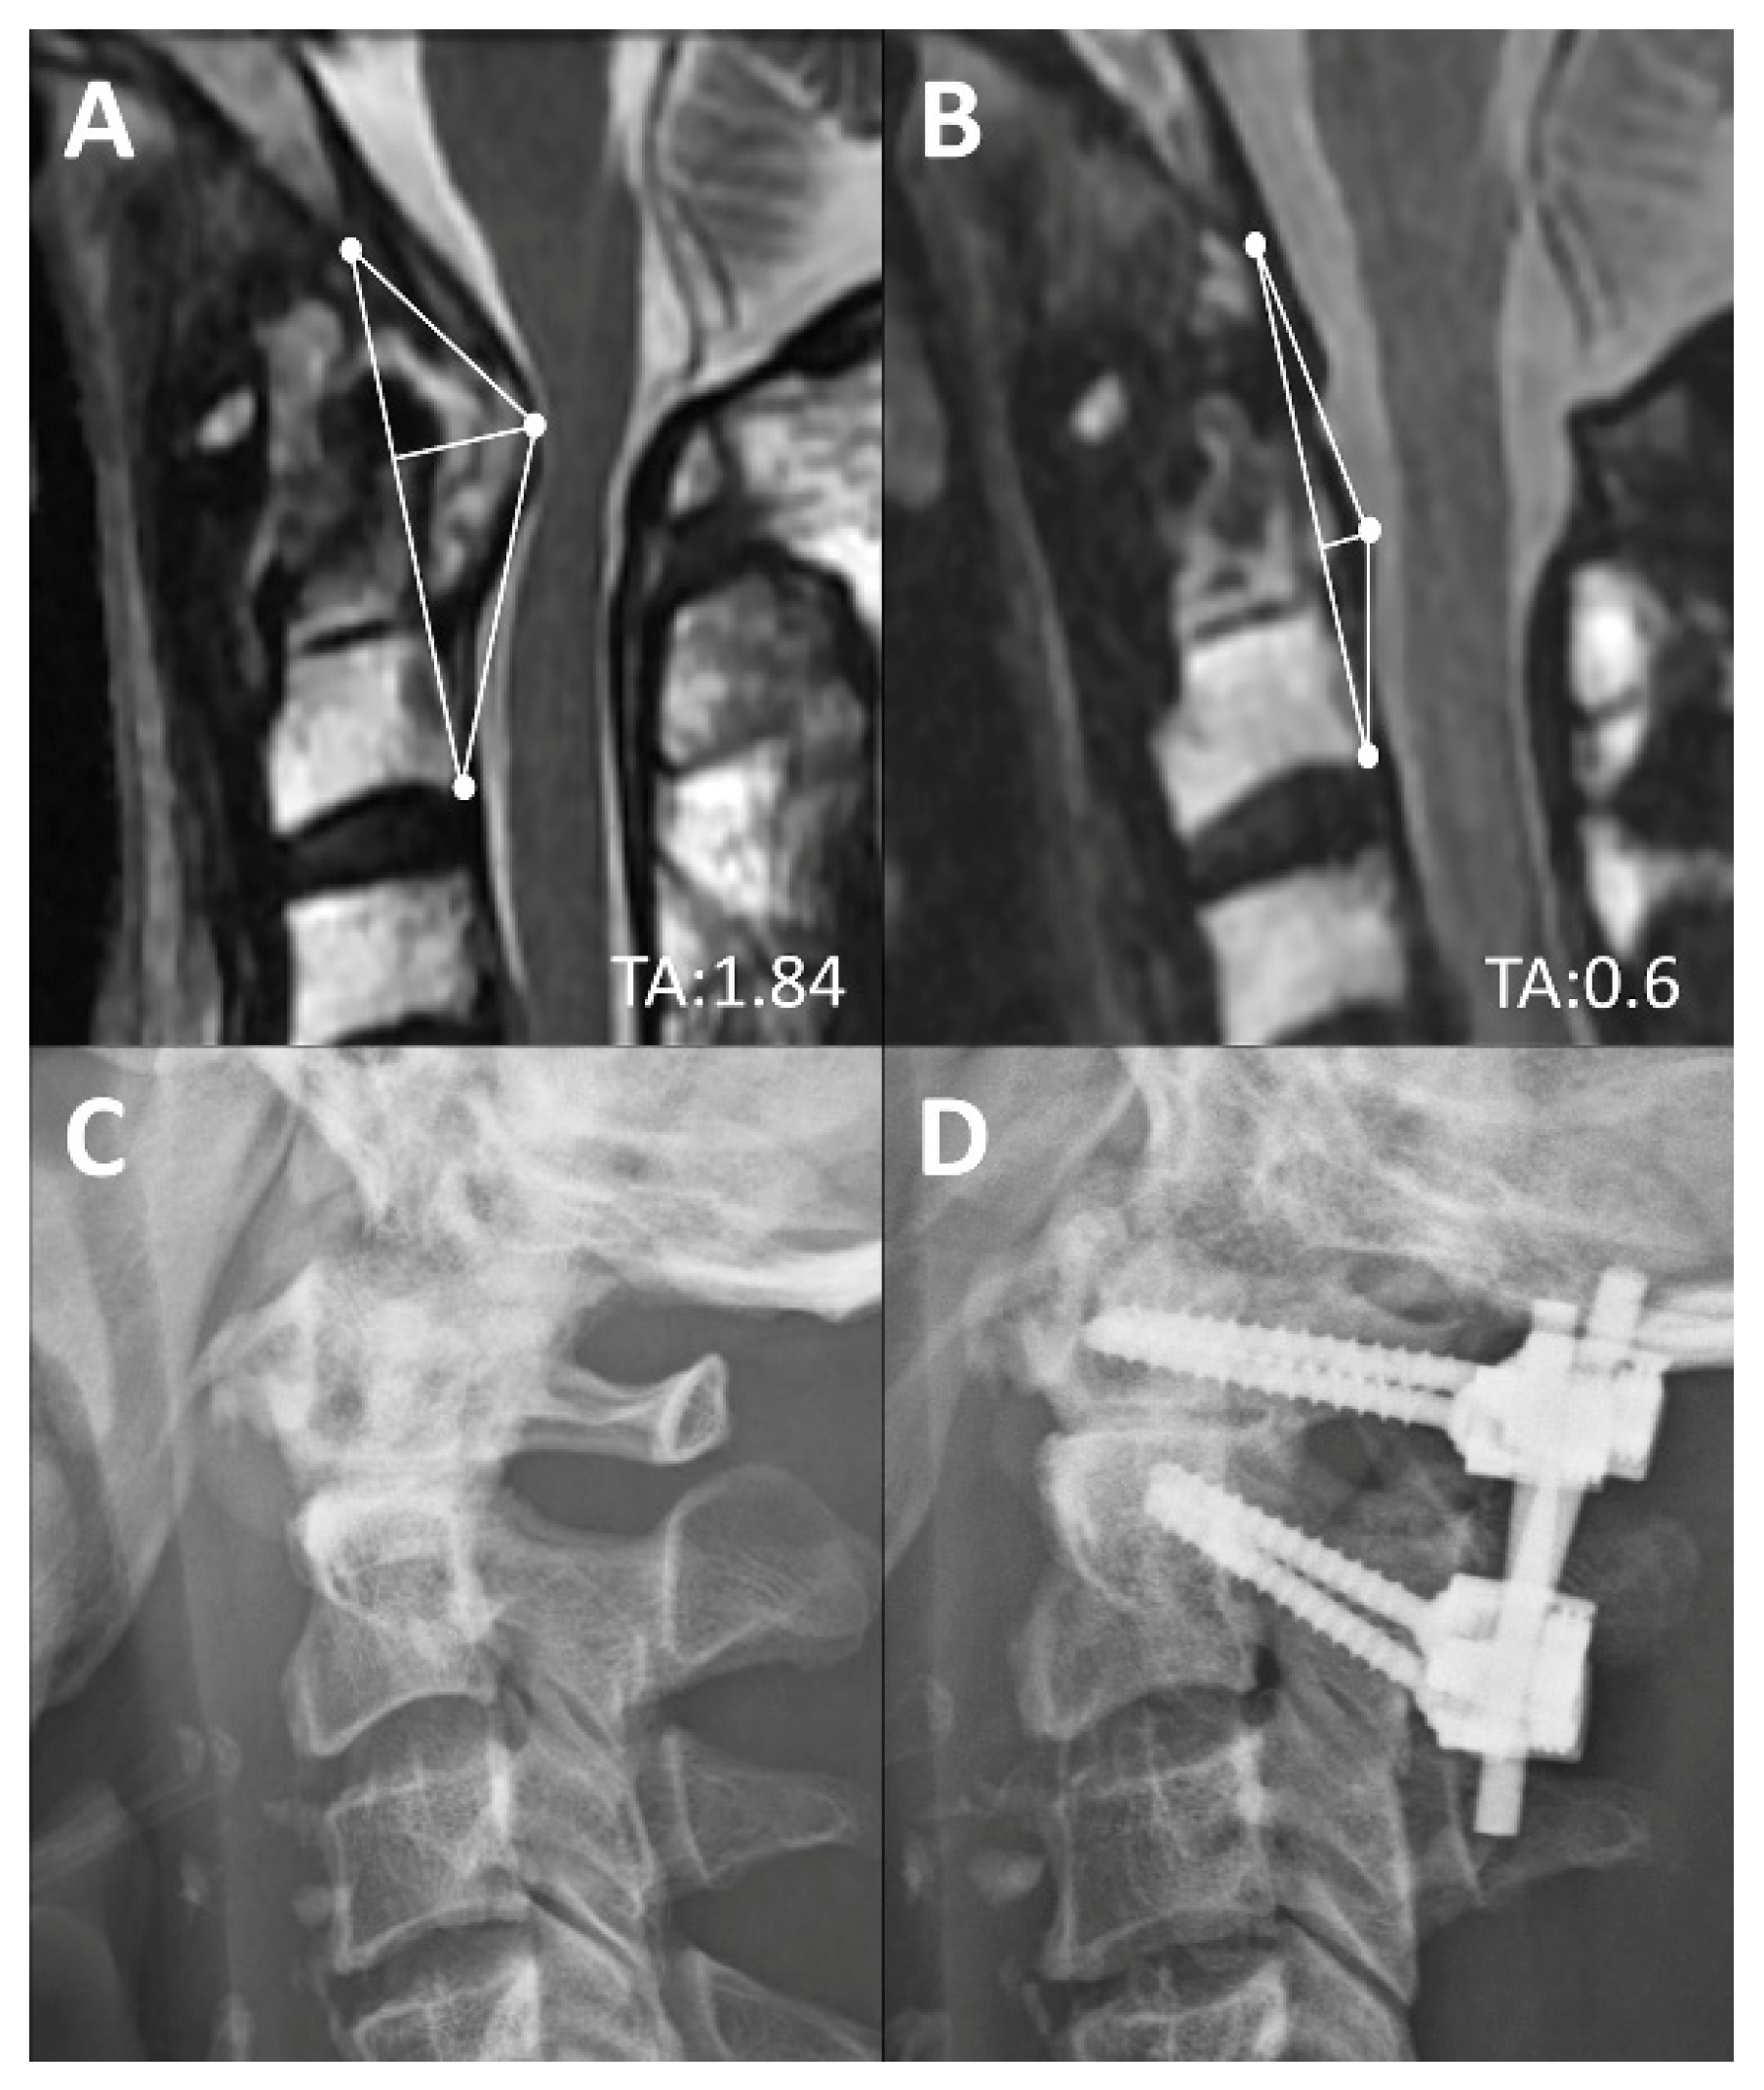

Figure 5.

Pre-op (A) and 2-year post-op (B) mid-sagittal T2 magnetic resonance image of a rheumatoid arthritis patient with retro-odontoid pannus formation. Post-operatively, the base of the TA remained the same and the height decreased from 0.93 to 0.3 cm after regression of the pannus. Pre-op (C) and two-year post-op (D) lateral radiographs.

The reduction of the TA of the CVJ also could correlate with the success of surgery and relief of myelopathic symptoms. Although in the present study, the two-year post-operative TA remained significantly larger than the normal control or the RA patients with a normal CVJ, significant neurological improvement was observed unanimously. In a subgroup analysis of two-year post-operation data, the key factor of TA normalization was dependent on the completeness of reduction. In patients who had complete reduction of malalignment, the average TA decreased from 1.52 ± 0.44 to 1.03 ± 0.39 cm2, which was close to the TA of the control group. In patients who achieved only partial reduction, despite clinical improvement, the TA values decreased from 1.81 ± 0.52 to merely 1.41 ± 0.2 cm2 at two-years post-operation. The results were compatible with the concept reportedly emphasized on the importance of reduction and posterior fixation in management of CVJ deformity [18,19,20,21]. In summary, to achieve best decompression, both the base and height of the TA should be addressed by surgery. For example, in complete reduction, the base of the triangle must decrease and the cranio-medullary angle improve immediately. After arthrodesis, the retro-odontoid soft tissue or pannus in patients with RA, continuously regressed at one-year and two-years post-operation, and this was compatible with published literature [22,23,24] (Figure 5).

Although reduction of the atlanto-axial subluxation and solid arthrodesis are always the goal of surgery, complete reduction was not always achievable in the series. The post-hoc analysis further divided the surgical cohort into two groups: Partial reduction and complete reduction patients. Patients’ TA of the complete reduction group was significantly lowered from 1.52 ± 0.44 pre-operation to 1.03 ± 0.39 cm2 at two-years post-operation, which was similar to that of the control and RA with normal CVJ groups. On the other hand, even though the TA of patients in the partial reduction group demonstrated a significant decrease two-years post-operation (from 1.81 ± 0.52 to 1.41 ± 0.2 cm2), the two-year post-operative TA of the partial reduction group was still significantly larger than that of the controls (p < 0.05).